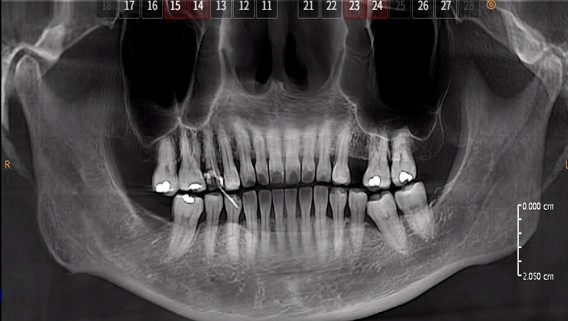

After endodontic treatment (root canal treatment), crown restoration is an in complete treatment, not an optional one:

2.Large defect/functional teeth (e.g., mandibular first molars, the main occlusal teeth): Crown or onlay restoration is mandatory;

1. Loss of hard tooth tissue due to caries and cavity preparation during treatment, decreased water content, and reduced fracture resistance;

4. Lack of restorative protection easily leads to reinfection of the root canal.